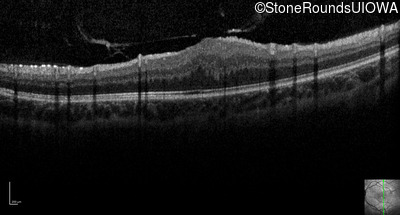

Optical Coherence Tomography - Right - 20/400

Exemplar